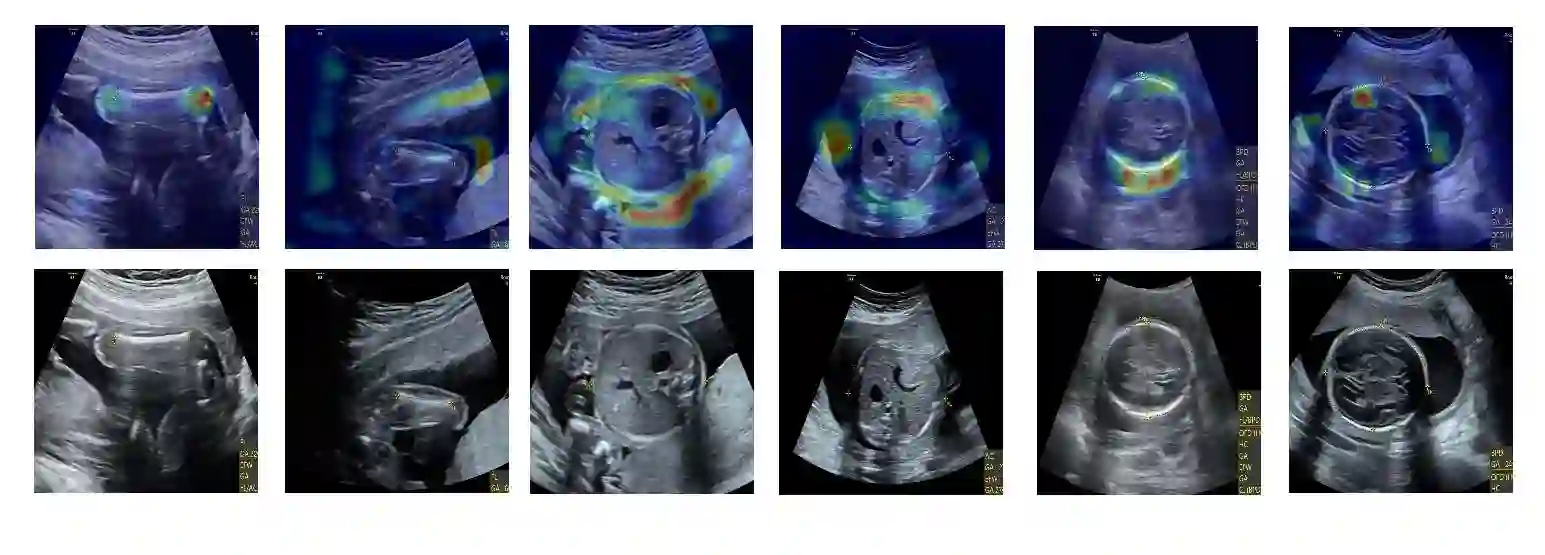

Although deep neural networks (DNN) have achieved state-of-the-art performance in various fields, some unexpected errors are often found in the neural network, which is very dangerous for some tasks requiring high reliability and high security. The non-transparency and unexplainably of Convolutional Neural Networks (CNN) still limit its application in many fields, such as medical care and finance. Despite current studies that have been committed to visualizing the decision process of DNN, most of these methods focus on the low level and do not take into account the prior knowledge of medicine. In this work, we propose an interpretable framework based on key medical concepts, enabling CNN to explain from the perspective of doctors' cognition. We propose an interpretable automatic recognition framework for the ultrasonic standard plane, which uses a concept-based graph convolutional neural network to construct the relationships between key medical concepts, to obtain an interpretation consistent with a doctor's cognition. Extensive experiments have empirically shown that our model can meaningfully explain the decision of the classifier and provide quantitative support.

翻译:尽管深度神经网络(DNN)在不同领域取得了最先进的性能,但在神经网络中经常发现一些出乎意料的错误,这对一些需要高度可靠和高度安全的任务非常危险。进化神经网络(CNN)的不透明和不可解释性仍然限制其在许多领域的应用,如医疗和财务等。尽管目前致力于直观DNN决策过程的研究,但这些方法大多侧重于低水平,没有考虑到以前对医学的了解。在这项工作中,我们提出了一个基于关键医学概念的可解释框架,使CNN能够从医生认知的角度解释。我们提议了一个超声波标准平面可解释的自动识别框架,它使用基于概念的图形神经网络来构建关键医学概念之间的关系,以获得与医生认知一致的解释。广泛的实验从经验上表明,我们的模型可以有意义地解释分类师的决定并提供定量支持。